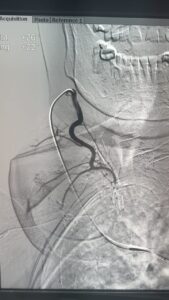

فى إنجاز طبى غير مسبوق داخل مصر، بل و على مستوى الشرق الأوسط، أعلن الدكتور محمود عبد العزيز غلاب – استشارى الأشعة التداخلية – عن نجاحه فى إجراء أول حالة من نوعها فى الأسكندرية لعلاج تضخم الغدة الدرقية عن طريق القسطرة الشريانية، و هو أسلوب حديث تم نقله من اليابان بعد تدريبه فى واحدة من أرقى الجامعات اليابانية المتخصصة في مجال الأشعة التداخلية.

تعد هذه الحالة الأولى من نوعها التى يتم فيها الدخول عبر القسطرة الشريانية إلى الشرايين المغذية للغدة الدرقية في الإسكندرية.

المريضة، وهى سيدة تبلغ من العمر 81 عامًا، كانت تعانى من تضخم شديد بالغدة الدرقية تسبب فى ضغط على القصبة الهوائية، مع تعدد النتوءات داخل الغدة، إلى جانب معاناتها من أمراض بالقلب حالت دون إمكانية خضوعها لأى جراحة. و بعد رفض حالتها من قِبل أكثر من استشارى جراحة نظراً لخطورة التدخل الجراحى، كان الحل الوحيد هو اللجوء إلى الأشعة التداخلية.

و بسبب كبر حجم الغدة و تعدد النتوءات فيها، لم يكن التردد الحرارى هو الخيار الأمثل، وعليه و بالتنسيق مع الدكتور محمد جلال الغاوي استشاري الغدد الصماء فقد قام الدكتور محمود غلاب أسلوبًا بالتدخل عبر الحقن بالقسطرة الشريانية، وهو ما مكّن من غلق الشرايين المغذية للنتوءات وبالتالى تقليص حجمهم و تحسين الأعراض بشكل ملحوظ.